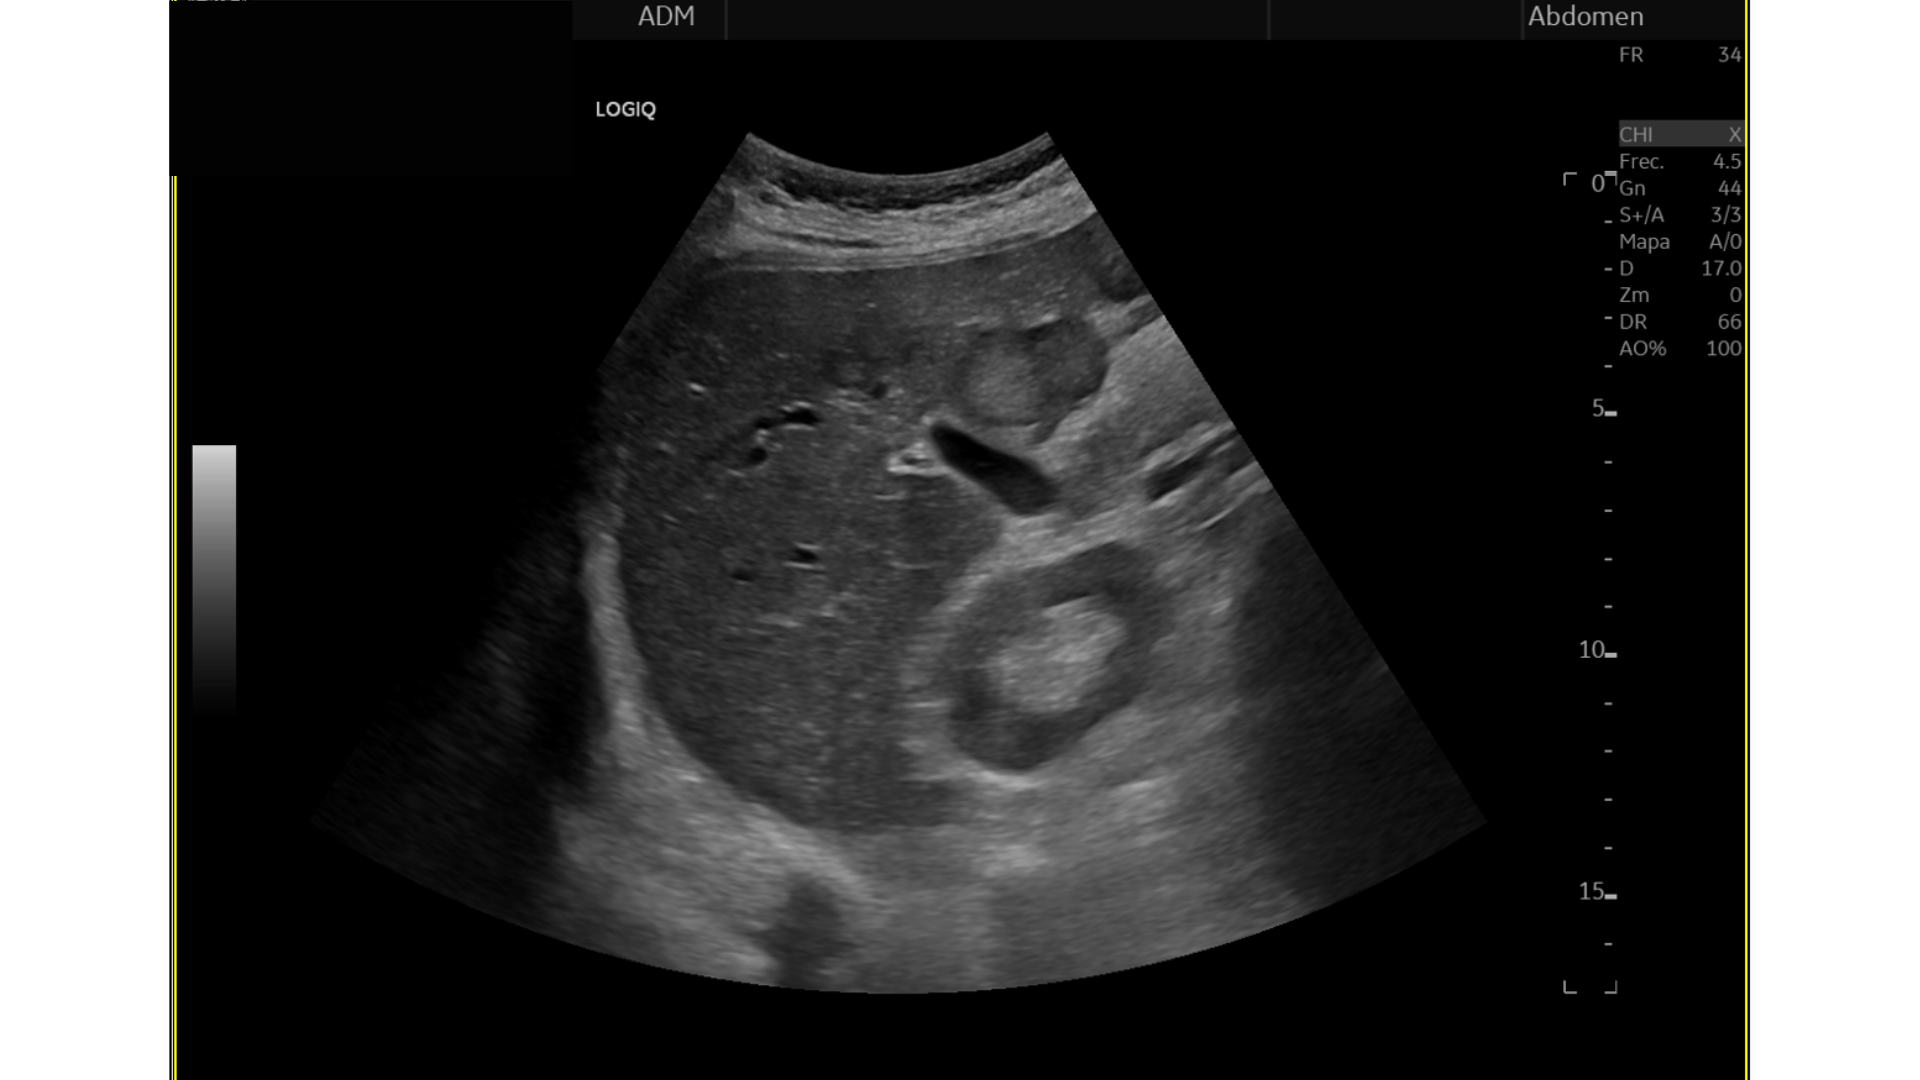

Eco Abdominal: Múltiples imágenes nodulares heterogéneas en ambos lóbulos hepáticos sugestivas de M1. Destaca imágen nodular, hipoecogénica en cabeza/cuerpo de páncreas de aprox. 17 mm, podría corresponderse con proceso neoformativo primario.